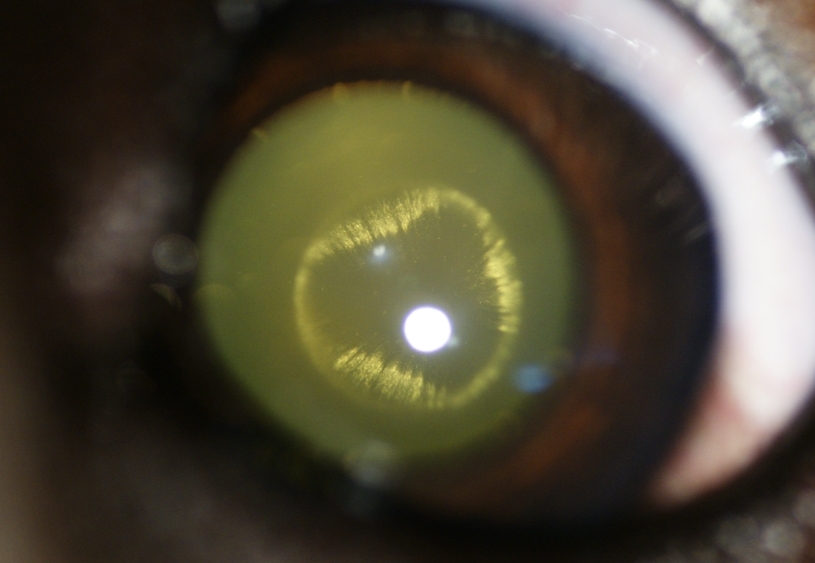

Cataracte périnucléaire postérieure chez un chiot

- 64532 (273.9 Kio) Consulté 2735 fois